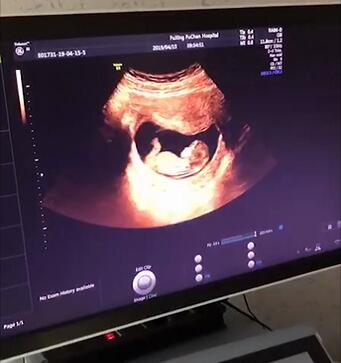

NT即胎儿颈项透明层,指胎儿颈背侧软组织和皮肤之间这一部分,通常是液体。在超声影像下,宝宝的皮肤看起来像条白线,皮肤下的液体则看起来是黑色,所以颈项透明层厚度就是指这里黑色的厚度。

56b7abf0de6a0bb0b95e7b5e7e40e4ff.jpg